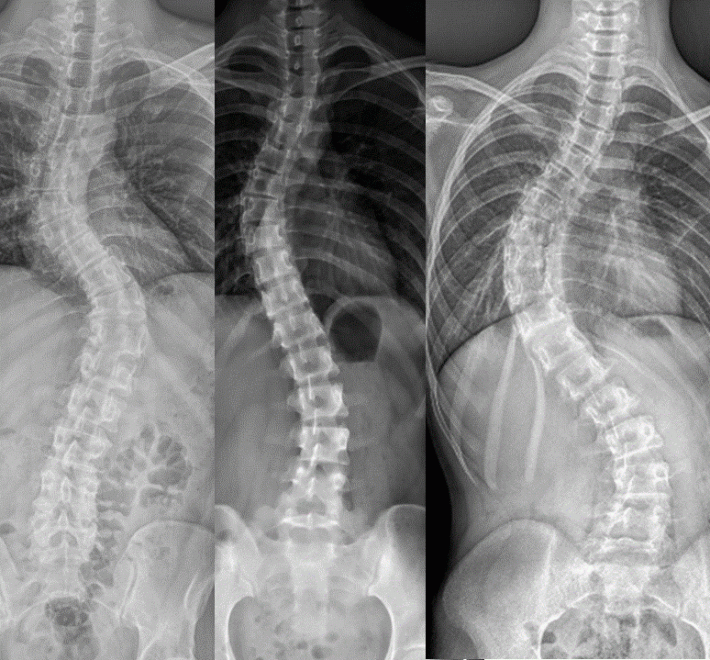

Computer-Navigated Minimally Invasive Surgery: A New Hope for Severe Scoliosis Correction with Over 80% Postoperative Improvement

Scoliosis is a common spinal condition that, if left untreated, can lead to physical deformities, impaired cardiopulmonary function, and even impact daily life.